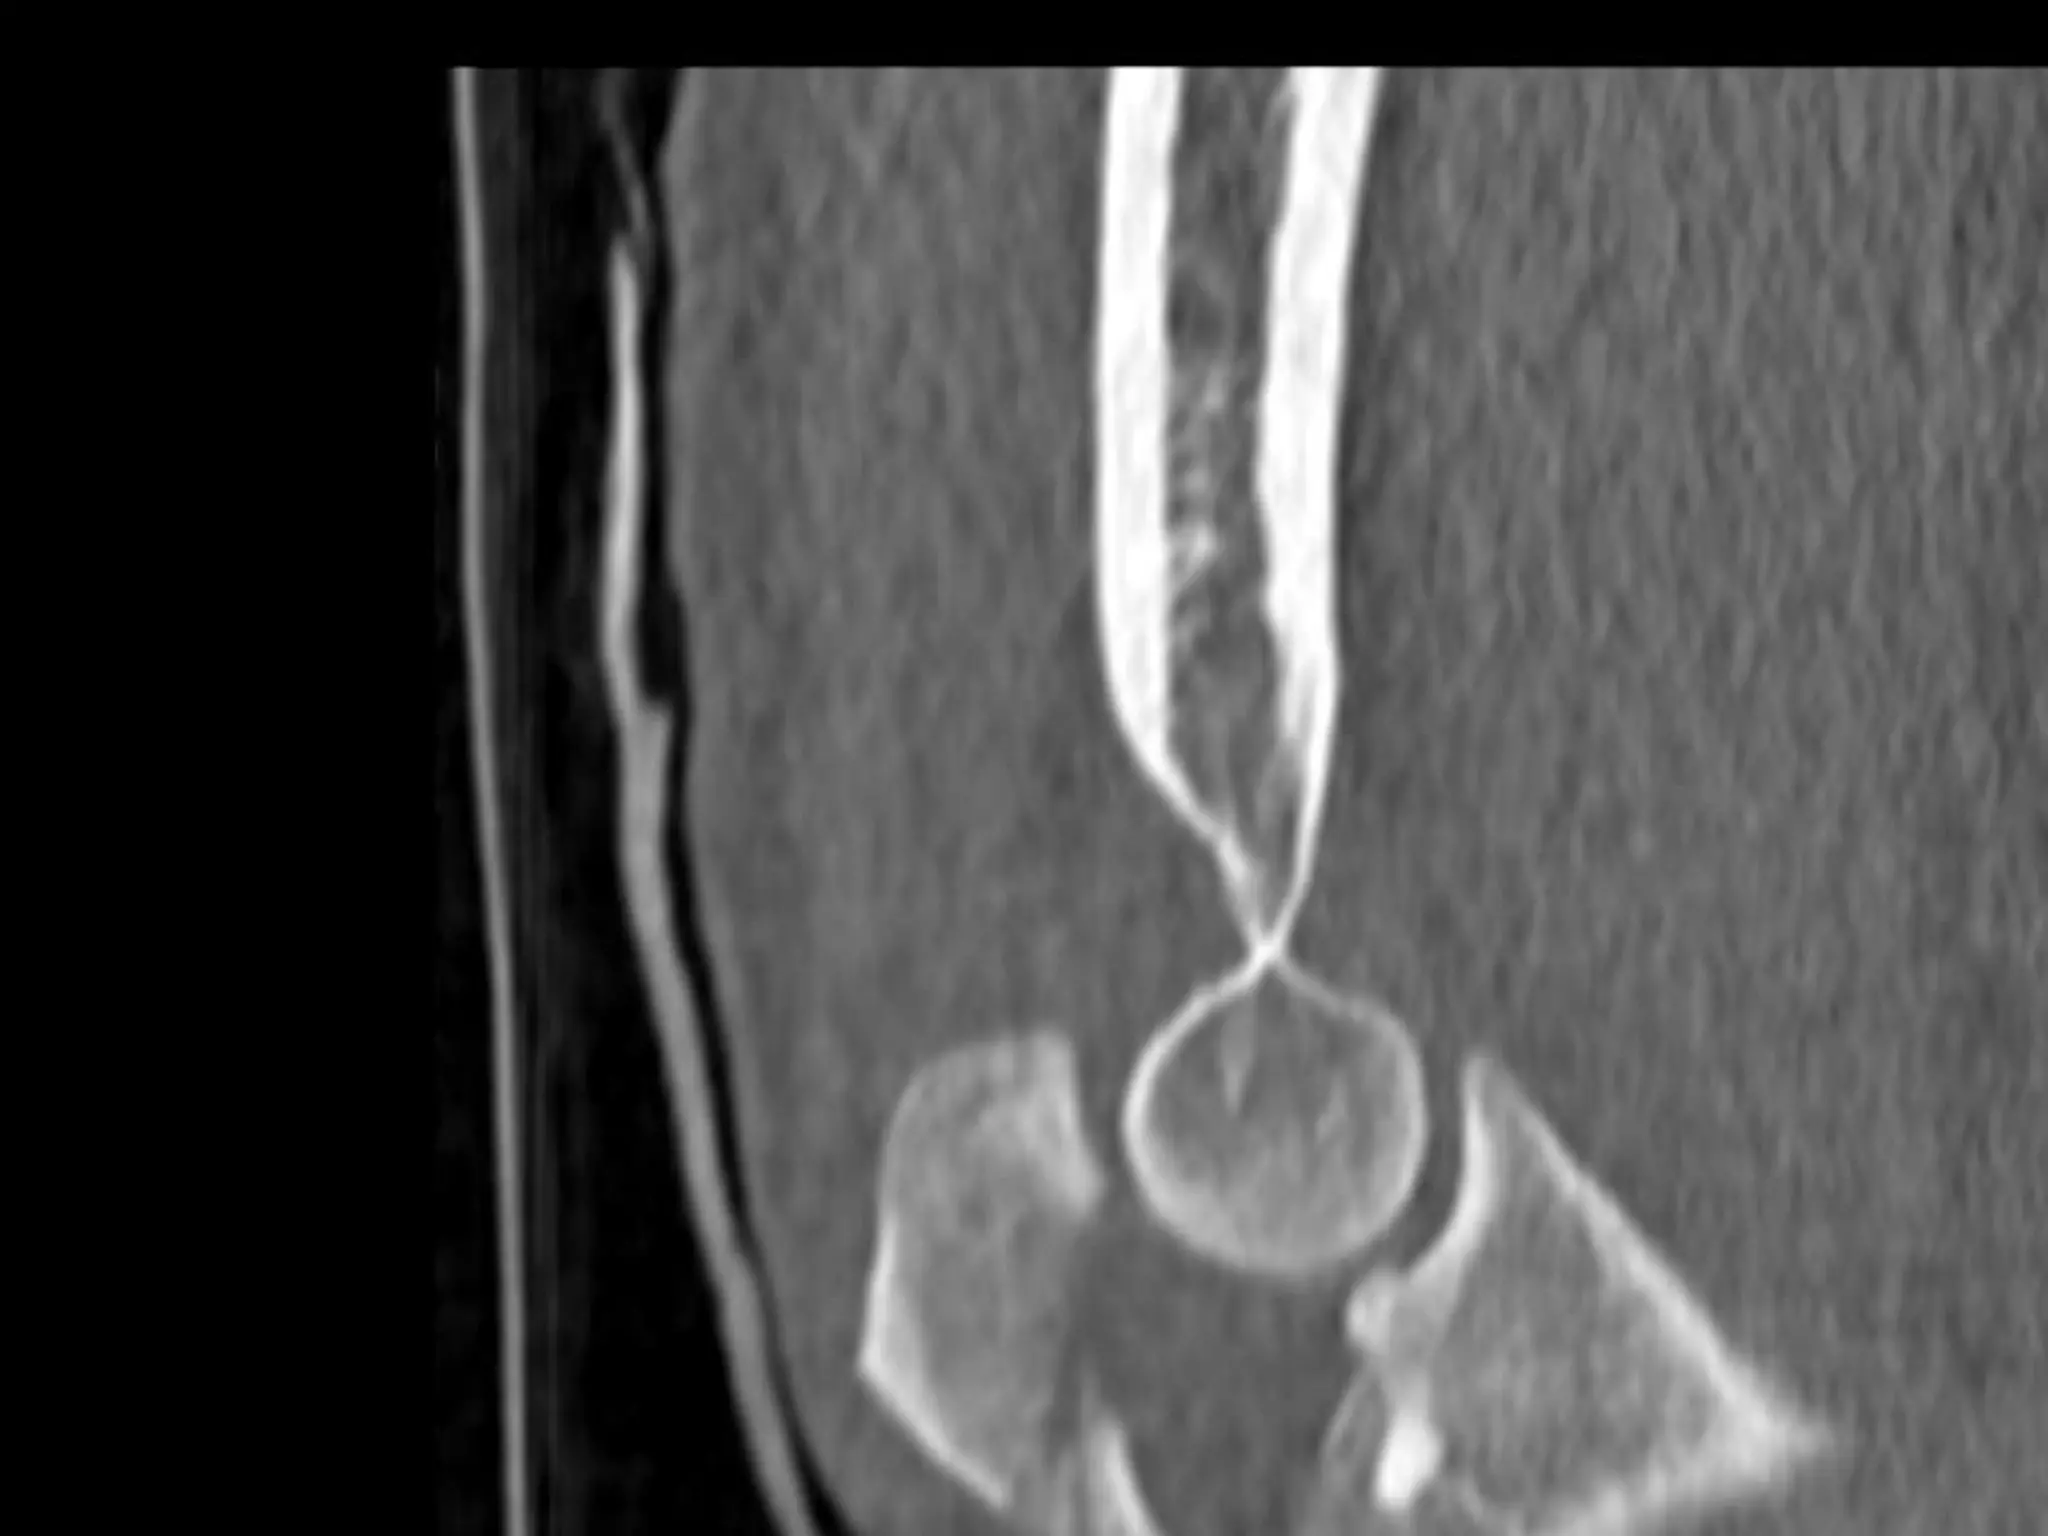

• Depth of prosthesis

• Version of prosthesis

• Size of the head